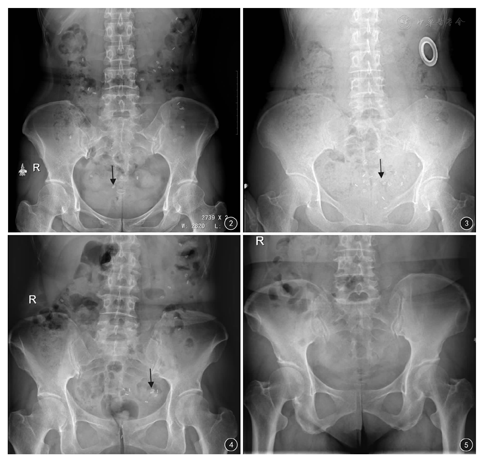

65例慢性功能性便秘患者中,慢传输型32例(图2),出口梗阻型13例(图3),混合型便秘2例(图4),正常传输型18例(图5)。其中2例慢传输型患者及5例出口梗阻型患者治疗过程中失访;随访成功58例患者,按其分型诊断接受了不同的治疗:出口梗阻型患者8例,经排粪造影及胃肠外科就诊,确定直肠前突及黏膜内脱垂,接受吻合器痔上黏膜环切钉合术,术后4周7例患者治疗有效,肛门梗阻及会阴部坠胀感改善;30例慢传输型、2例混合型及18例正常传输型患者经保守治疗后,治疗有效患者分别为28例、2例、16例,排便困难及腹痛、腹胀改善(见表1)。无效5例。